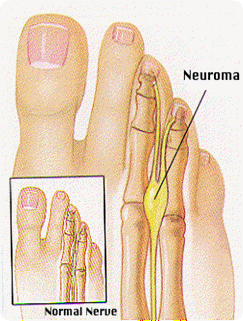

Neuroma de Morton

Neuroma de Morton Neuroma de Morton

¿Qué es el Neuroma de Morton?

Los nervios que transmiten mensajes desde los dedos hasta el cerebro pasan entre los metatarsianos (los huesos largos que están a continuación de los dedos).

La debilidad del arco plantar puede hacer que los metatarsianos pellizquen el nervio, provocando su inflamación. Esto ocurre más frecuentemente entre el 3º y 4º metatarsiano causando dolor o sensación de entumecimiento en estos dos dedos.

A veces se debe a un neuroma o un tumor no canceroso en los nervios digitales plantares (situados entre los dedos). También puede desarrollarse debido a que los zapatos aprietan demasiado, haciendo presión sobre el nervio.

Esto se agrava en los deportistas, especialmente en los corredores y en los futbolistas quienes, al correr o al golpear la pelota con el pie, someten estos nervios a mayor presión.

¿Cuáles son los síntomas del Neuroma de Morton?

• Dolor en la parte anterior del pie o a un lado de un dedo y en el lado adyacente del dedo contiguo.

• Dolor al apretar la punta del pie.

• Dolor al presionar entre los metatarsianos.